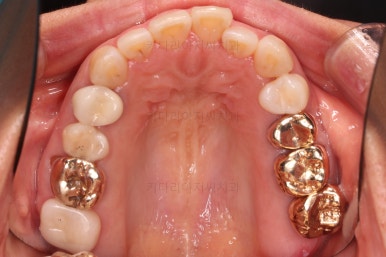

초진 시 입안의 모습입니다.

아랫니 큰 어금니 하나가 없어서 임플란트를 원하셨던 환자분이셨어요.

앞니가 조금 삐뚤고, 아랫니는 사이사이에 틈새가 있었지만 전체적인 교정은 원치 않으셨어요.